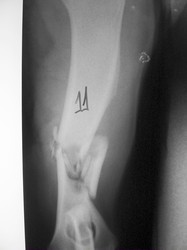

PRÁCTICAS CURSO DE FIJACIÓN EXTERNA PERFECCIONAMIENTO.

Húmero.